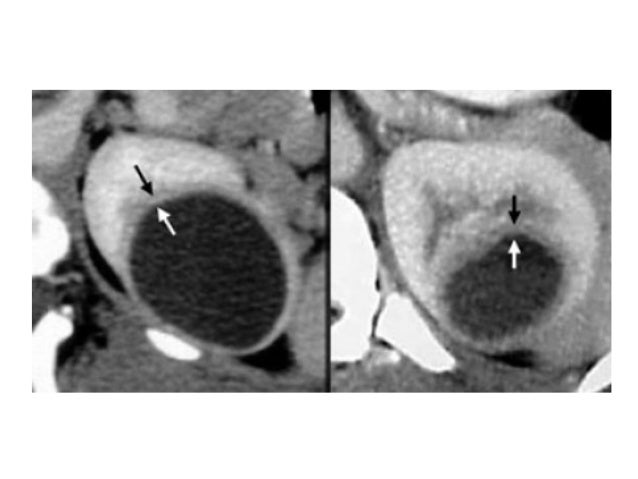

ΠΠ’ ΠΠΠ ΠΈ Π·Π°Π±ΡΡΡΠΈΠ½Π½ΠΎΠ³ΠΎ ΠΏΡΠΎΡΡΡΠ°Π½ΡΡΠ²Π°. Π‘ΠΏΡΠ°Π²Π° (ΡΠΈΠ½ΡΡ ΡΡΡΠ΅Π»ΠΊΠ°) ΠΏΡΠΎΡΡΠ°Ρ ΠΊΠΈΡΡΠ° (Bosniak 1), ΡΠ»Π΅Π²Π° (ΠΊΡΠ°ΡΠ½Π°Ρ ΡΡΡΠ΅Π»ΠΊΠ°) ΠΊΠΈΡΡΠ° Bosniak 4 (Π·Π»ΠΎΠΊΠ°ΡΠ΅ΡΡΠ²Π΅Π½Π½Π°Ρ ΠΎΠΏΡΡ ΠΎΠ»Ρ)

ΠΠ Π’ ΠΠΠ ΠΈ Π·Π°Π±ΡΡΡΠΈΠ½Π½ΠΎΠ³ΠΎ ΠΏΡΠΎΡΡΡΠ°Π½ΡΡΠ²Π°. ΠΡΠΎΡΡΠ°Ρ ΠΊΠΈΡΡΠ° ΠΏΡΠ°Π²ΠΎΠΉ ΠΏΠΎΡΠΊΠΈ (Bosniak 1)